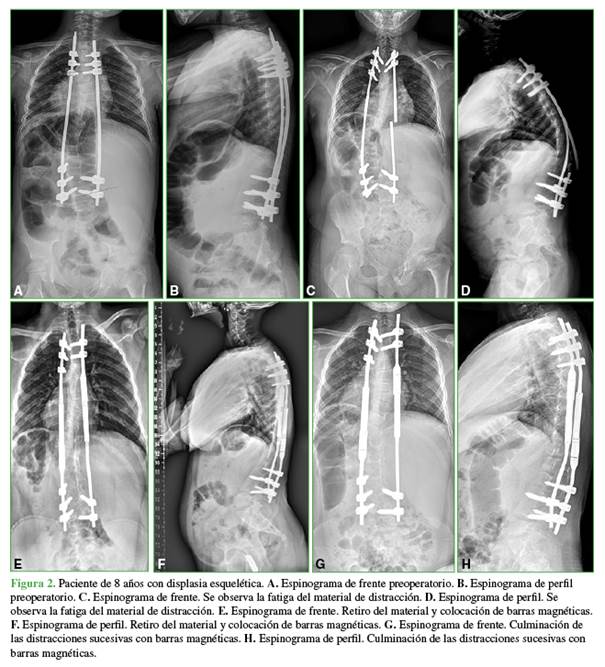

Se evaluó a 37 pacientes, 19 niñas y 18 niños, con una edad promedio de 8.2 años en el momento de la cirugía (rango 4-12). Las etiologías de la ECT eran: escoliosis neuromuscular (atrofia medular espinal, miopática, encefalopatías crónicas no evolutivas) (17 pacientes), escoliosis sindrómica (Silver-Rusell, William, Prader-Willi, Escobar, Marfan, neurofibromatosis, genéticos, displasia esquelética) (14 pacientes), escoliosis idiopática infantil (3 pacientes), escoliosis congénita (3 pacientes) (Figura 1).

Las conversiones a BM se realizaron en pacientes con escoliosis de origen sindrómico (6 casos), escoliosis congénita (1 caso), escoliosis neuropática (1 caso) y en otro con escoliosis idiopática infantil tratada desde los 2 años de vida con corsé de yeso, bajo anestesia, sucesivos corsés termoplásticos y barras de crecimiento tradicionales, al agotarse la posibilidad de elongación, se decidió la conversión a BM (Figura 2).